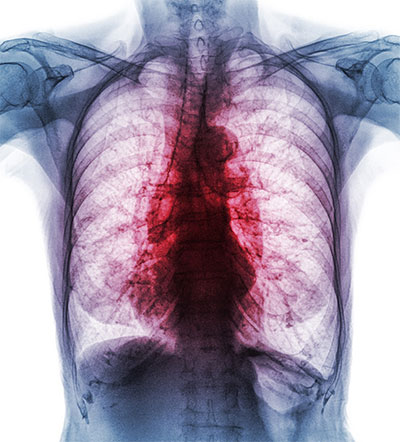

Interstitial lung disease causes inflammation or scarring of the lung tissue.